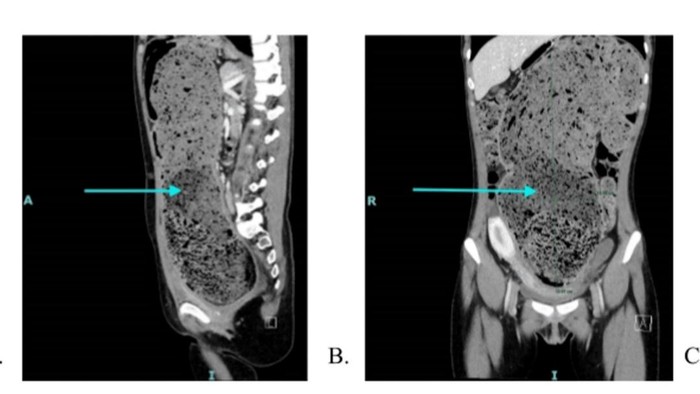

Sampai akhirnya, dokter melakukan pemeriksaan CT scan untuk melihat apa yang ada di dalam tubuhnya. Terlihat, di saluran pencernaan wanita itu dipenuhi dengan tinja atau feses, yang dikenal sebagai impaksi feses.

Selain itu, dari CT scan menemukan wanita itu memiliki kolon sigmoid berlebih berdiameter 15 cm. Kolon yang panjang tidak normal yang melipat dan melilit di rongga perut, bisa juga menyebabkan sembelit.

Kolon tersebut seperti meregang dan berisi banyak tinja.